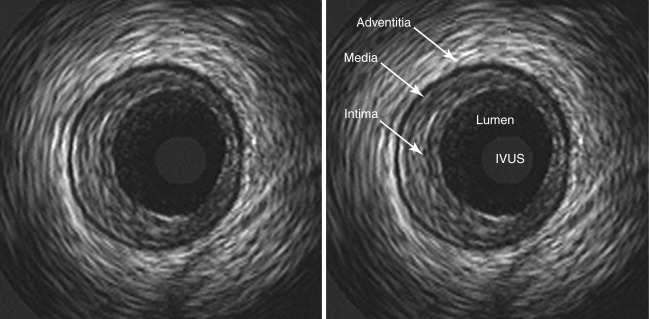

IVUS (Intravascular Ultrasound) uses sound waves to map the total volume of plaque inside an artery. Think of it like sonar, it tells you how much plaque is physically taking up space. IVUS is the workhorse of plaque regression trials.

IVUS images pictured above. An ultrasound probe goes inside the artery.